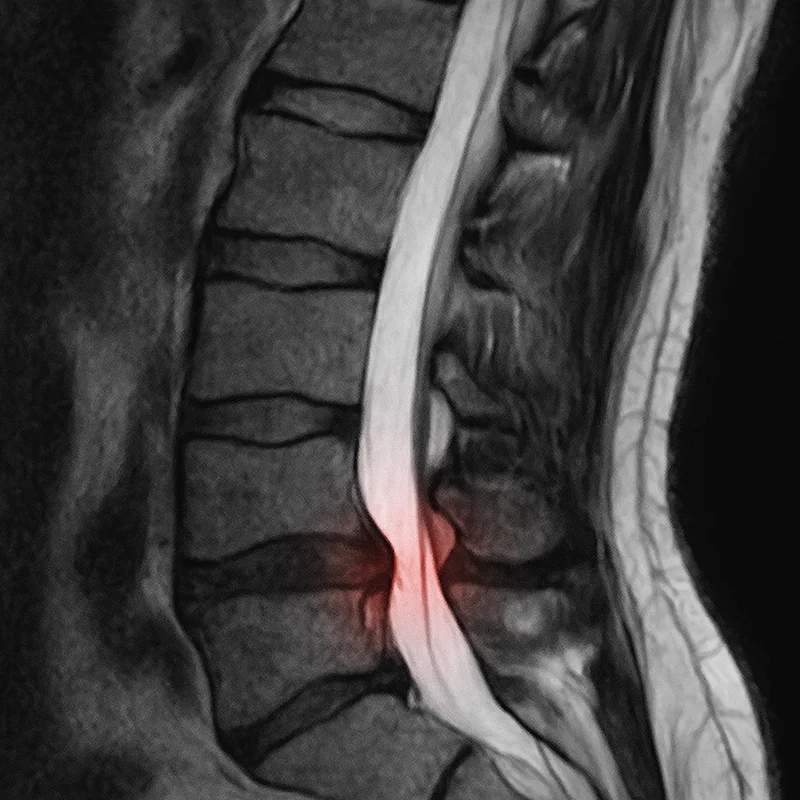

Herniated or bulging discs are the most common cause I see. The disc material pushes out and puts direct pressure on the nerve root. Sometimes patients don’t even remember a specific injury—it can develop gradually from years of poor posture or repetitive strain. If you’re dealing with disc issues, you might find my post on herniated disc treatment options helpful.

Spinal stenosis happens when the canal housing your spinal cord narrows, typically from age-related changes. This crowds the nerve roots and can trigger sciatic symptoms, especially when standing or walking.